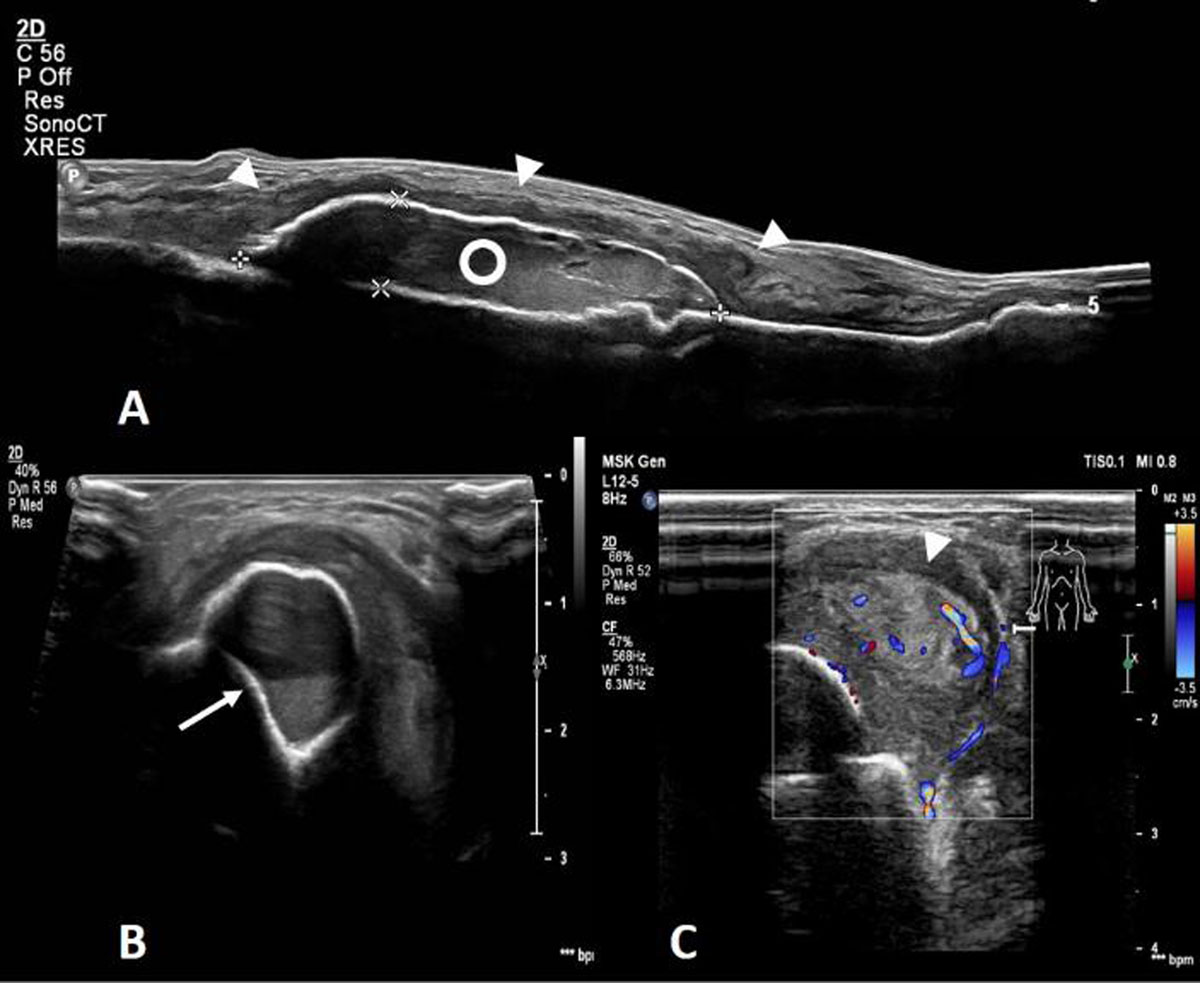

Radiographs (Figure 1) demonstrated a soft tissue swelling on the medial side of the tibial shaft outlined by a thin calcified rim (arrowheads). A smaller, similar lesion could be seen more cranially (arrow). Ultrasound (US) (Figure 2A-C) showed a subperiosteal collection (circle) with an internal fluid-fluid level (arrow) as well as calcification of the surrounding periosteum. The calcified periosteum is surrounded by a heterogeneous, vascularized soft tissue cuff (arrowheads). MRI (Figure 3A-D) demonstrated a subperiosteal collection with signal properties of a chronic hematoma (triangle): T1/T2-isointense in the periphery of the lesion but T1-iso/T2-hyperintense in the centre (Figure 3C and 3A, respectively, for T1- and T2-weighted imaging). Moreover, there was the additional finding of a T2-hyperintense, T1-isointense, fat-poor (Figure 3B), enhancing tissue (star in Figure 3D), located medially and posteriorly with respect to the hematoma, corresponding to the described soft tissue cuff on US. These MRI features were suggestive of a plexiform neurofibroma of the saphenous nerve, that has caused an ossifying subperiosteal hematoma due to chronic erosion of the tibial cortex. Note the smooth cortical thinning on MRI (dashed arrow), the mass effect exerted on the tibialis posterior and flexor digitorum muscles as well as the surrounding soft tissue oedema.

Figure 2